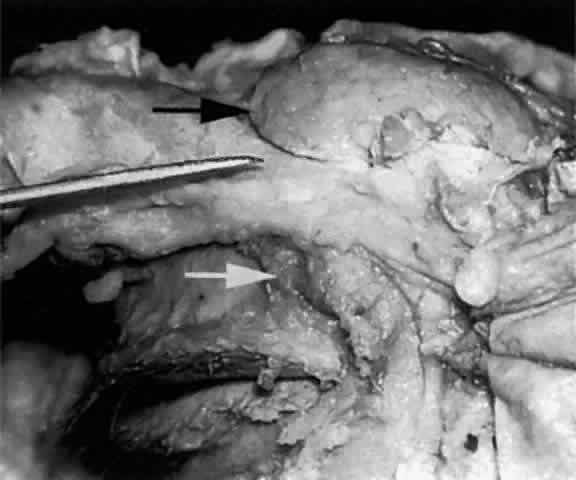

The main lacrimal gland resides in the superotemporal orbit, partially within a shallow bony fossa in the lateral angular process of the frontal bone (fossa glandula lacrimalis). The gland is situated between the eyeball below and the curved orbital wall above, giving it a somewhat compressed and curved shape. It may extend inferiorly to the lateral canthal tendon. The lateral horn of the levator aponeurosis crosses the gland anteriorly, separating it into a larger superior or orbital lobe and a smaller inferior or palpebral lobe (Fig. 2). The division is incomplete because the larger orbital lobe is connected to the smaller palpebral lobe posteriorly by a bridge of glandular tissue, draining tubules, and Müller's muscle, which is attached to the underside of the levator muscle and aponeurosis. The lacrimal gland is surrounded by fibrous tissue that is attached superiorly to the periosteum of the frontal bone and inferiorly to the orbital portion of the zygomatic bone.1

Fig. 2. With the roof and lateral wall of the left orbit removed, this cadaver dissection demonstrates the orbital lobe (black arrow) and the palpebral lobe (white arrow) separated by the lateral horn of the levator aponeurosis (pointer).

The almond-shaped orbital lobe (see Fig. 2) represents approximately 65% to 75% of the gland and measures 20 mm long × 5 mm thick × 12 mm wide.2 Its sharp anterior border rests behind the superior orbital rim and is covered by the orbital septum (Fig. 4) and a portion of the temporal aspect of the central preaponeurotic fat pad (Fig. 5). Posteriorly, its rounded border is supported by a large superotemporal fat pad at the plane of the posterior pole of the globe.3 The convex superior surface is suspended from the periorbita of the lacrimal gland fossa of the frontal bone. The inferior border is convex and attached to the sheath of the levator aponeurosis. Its lateral border is smooth and convex in contour with the bony fossa.

The inferior or palpebral lobe of the lacrimal gland (see Fig. 2) represents approximately 25% to 35% of the gland and lies beneath the levator aponeurosis in the subaponeurotic space. It extends anteriorly beyond the orbital margin to lie in the lateral portion of the superior fornix. The palpebral lobe can be seen through the conjunctiva when the eyelid is elevated or everted (Fig. 6).